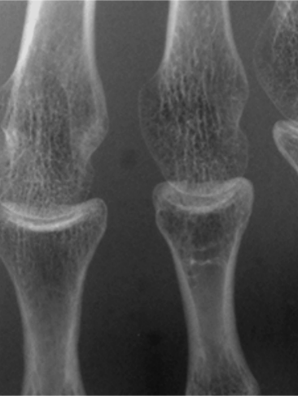

グリッド無し

ピクセル・アラインド・グリッド

一般的なグリッド

通常グリッド+グリッド目除去処理